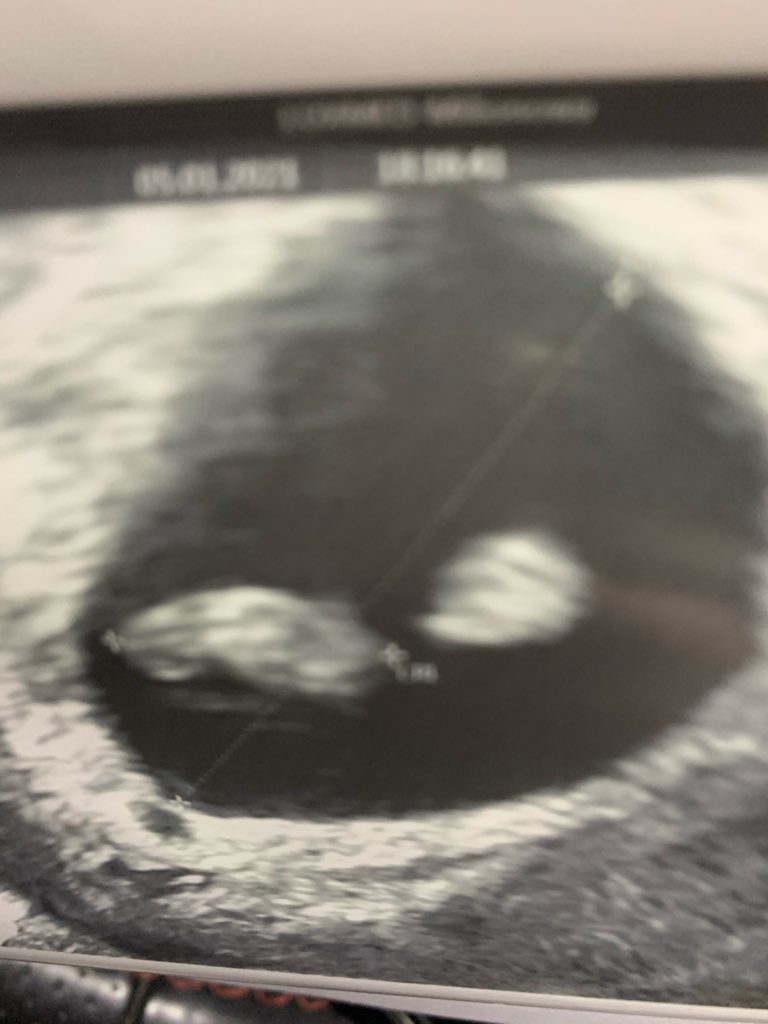

Melduje się po USG. Ciąża żywa, jest serduszko i maluszek ma 12mm 🥰 wg Usg 7t3d i termin na 17.08 😁

• IMG_2820.jpg

62,4 KB · Wyświetleń: 105